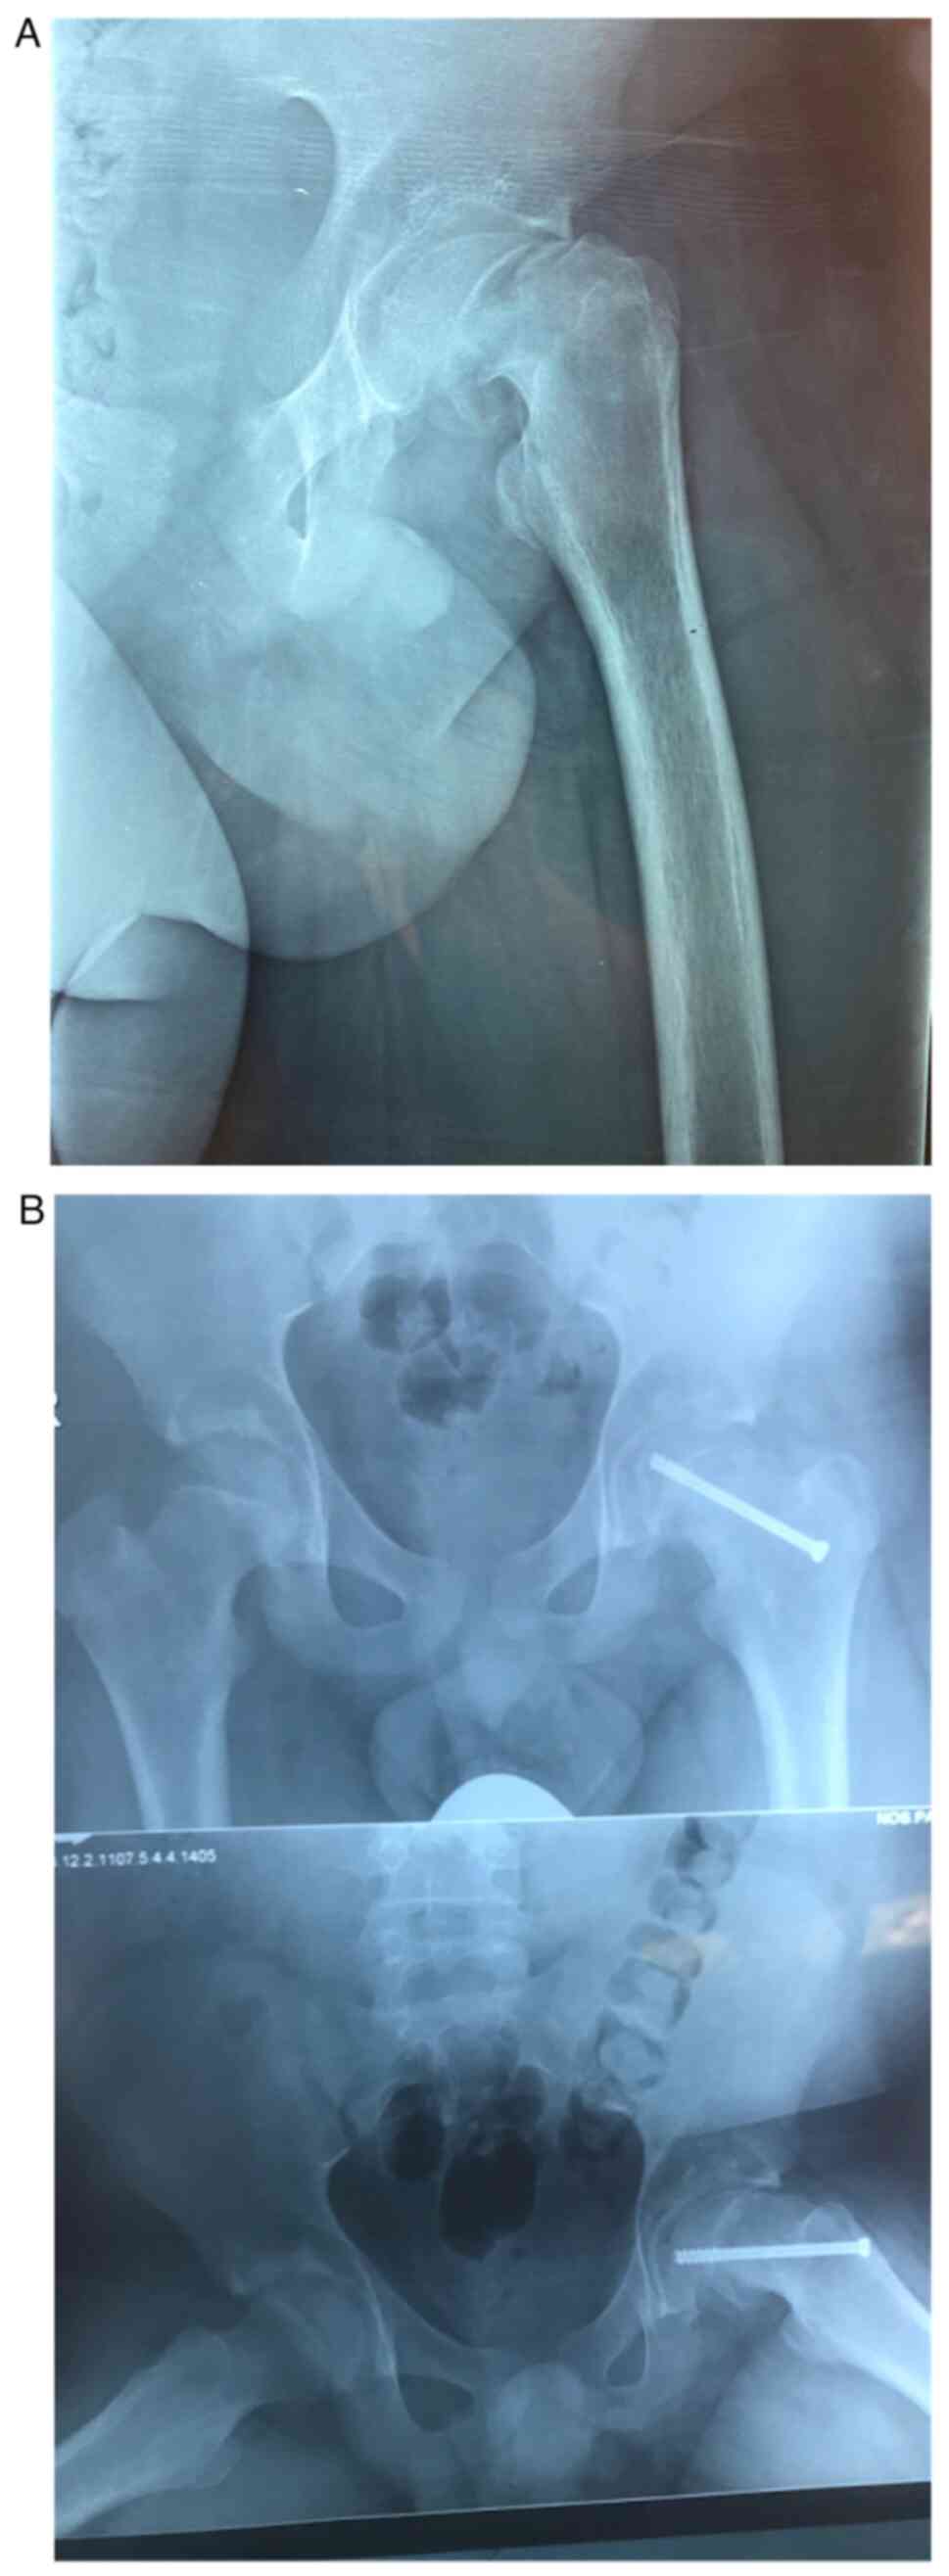

Acute‑on‑chronic slipped femoral epiphysis following posterior spinal fusion due to idiopathic scoliosis: Case report

The aim of this case report is to present a rare case of acute slipped femoral capital on a chronic slipped capital femoral epiphysis (SCFE) after spinal fusion due to idiopathic scoliosis. A 14 year old male patient underwent posterior spinal fusion due to idiopathic thoracic scoliosis. Post‑operatively, the patient presented with acute pain in the left hip and a reduced range of motion, which revealed acute SCFE. The patient was then referred to the Second Orthopaedic Department of Agia Sofia Children Hospital in Athens, and underwent percutaneous pinning of the left femur, after which he was discharged uneventfully. The follow up was excellent with no impact on the patient's daily life. The case described is extremely rare in the current literature. The significance of the pre‑operative planning is underlined by this case, as well as the need for the spinal surgeon to be aware of the possibility of acute pain in the hip in young adolescents, as SCFE is more common amongst this demographic.

Figure 2